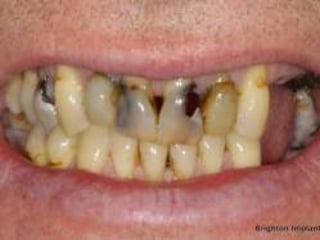

Contra-Indications

2. Non-Restorable tooth